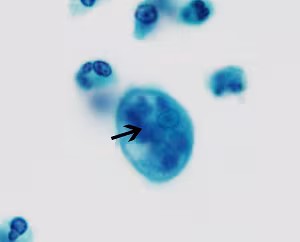

E. gingivalis trophozoites stained with trichrome.

There is no known cyst stage for Entamoeba gingivalis; trophozoites measure 10-20 µm. Trophozoites possess a single nucleus that contains a small, centrally-located karyosome and fine peripheral chromatin. The cytoplasm often contains ingested leukocytes, bacteria and other debris, very rarely red blood cells. The trophozoites may also extend agranular pseudopodia while the main cell cytoplasm remains granular in appearance. Living specimens can move quickly.

Identification of E. gingivalis is usually made by the finding of trophozoites in scrapings of the gums and teeth; trophozoites may be seen ingesting white cells and epithelial cell nuclei. Two genetic sub types exist, the ST1 and ST2-kamaktli subtypes, though any clinical significance or morphologic differences between these two have not been investigated at the time of writing. E. gingivalis may be found in sputum on rare occasions or detected in cervical Pap smears. As such, it is important to differentiate them from the morphologically-similar trophozoites of E. histolytica, which may be found in sputum from pulmonary abscesses and invading the female genital tract.